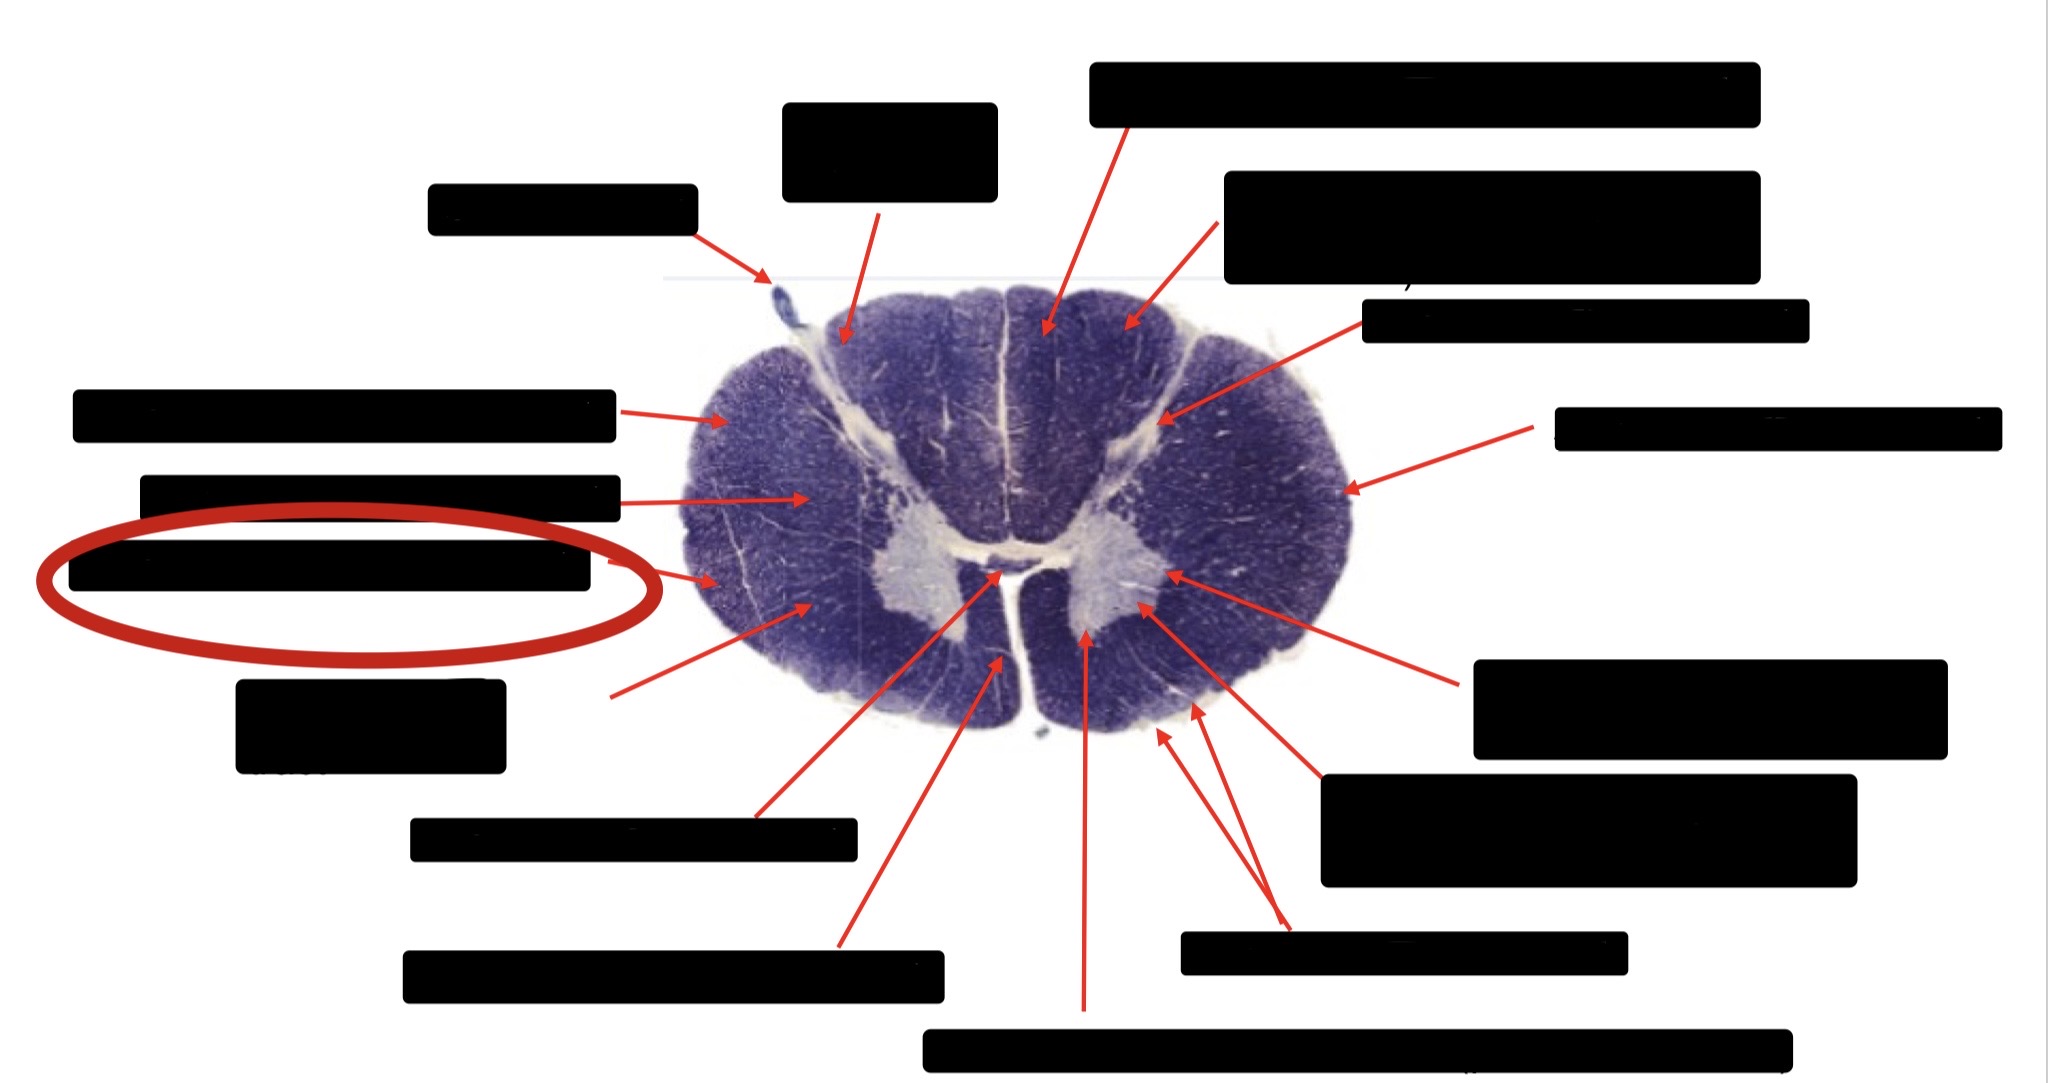

Posterior Column

Large Fiber Entry Zone

Posterior Spinocerebellar Tract

Clarke’s Nucleus

Anterior Spinocerebellar Tract

Ventral Root Fibers

Central Canal

Lissauer’s Tract & Small Fiber Entry Zone

Substantia Gelatinosa

Lateral Corticospinal Tract

Spinothalamic Tract

Anterior Horn Motor Neurons (Distal Muscles)

Anterior Horn Motor Neurons (Proximal Muscles)

Dorsal Rootlet

Lateral Horn